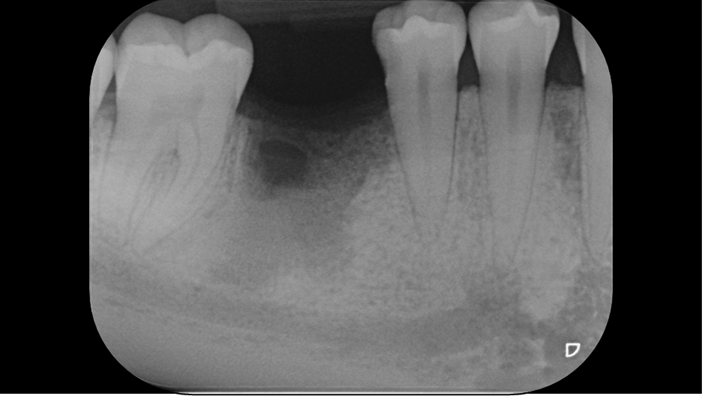

Clinical case: # 46 implant placement & GBR using i-Gen membrane for significant vertical resorption & mixed bone defect

- Courtesy of Dr. Iulian Filipov, Romania -

AnyRidge, mandibular posterior, i-Gen, resorption, bone defect, bone regeneration, space management, #46, GBR, Dr. Iulian Filipov

AnyRidge implant system, i-Gen